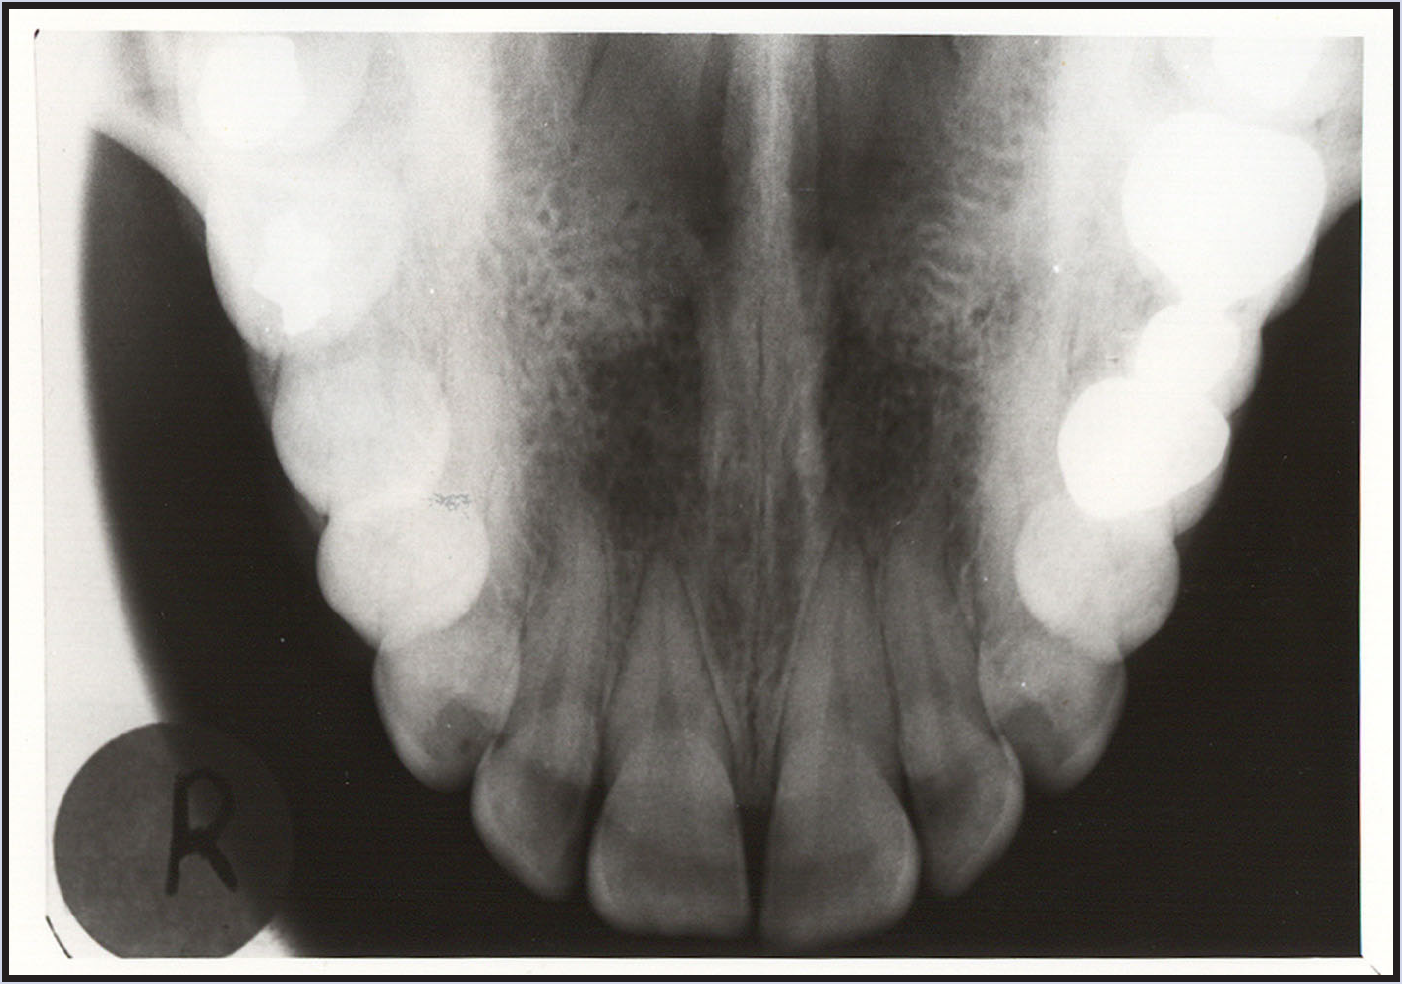

Figure 1 - Periapical Image

Figure 1

The purpose of the intraoral periapical examination is to obtain a view of the entire tooth and its surrounding structures, as in Figure 1. Two exposure techniques may be employed for periapical radiography: the paralleling technique and the bisecting angle technique. The paralleling technique is the preferred method. This technique provides less image distortion and reduces excess radiation to the patient. The paralleling technique should always be attempted before other techniques. The bisecting technique can be employed for patients unable to accommodate the positioning of the paralleling technique. Candidates may include those with low palatal vaults and children. Disadvantages to the bisecting technique include image distortion and excess radiation due to increased angulations involving the eye and thyroid glands. Regardless of the technique, however, the rules of radiography referred to earlier must be followed.